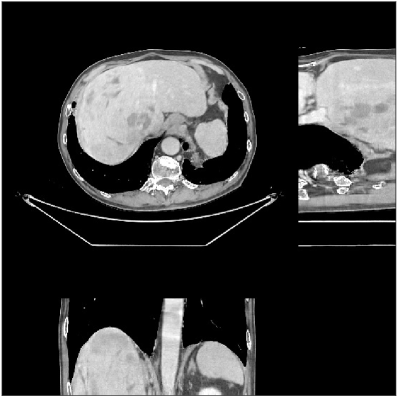

We evaluate the behavior of the PWLS-ULTRA method (with ) for 3D cone-beam CT data with . Fig.Β 2 shows the central slices along three directions for the underlying (true) XCAT phantom volume. We reconstruct the volume from low-dose CT measurements. Fig.Β 2 shows the RMSE and SSIM of PWLS-ULTRA for various choices of , the number of clusters (patch size and patch stride ). Rich models (large ) produce better reconstructions compared to using a single ST (). For the piece-wise constant phantom, clusters works well enough, with only a small additional RMSE or SSIM improvement observed for larger . Larger values of led to sharper image edges.

Fig.Β 5 shows the reconstructions and the corresponding error (magnitudes) images (shown for the central axial, sagittal, and coronal planes) for FDK, PWLS-EP, and PWLS-ULTRA () with the patch-based weights. Compared to FDK and PWLS-EP, PWLS-ULTRA significantly improves image quality by reducing noise and preserving structural details (see zoom-ins). Fig.Β 6 shows the RMSE for each axial slice in the PWLS-EP and PWLS-ULTRA (with the weights ) reconstructions. PWLS-ULTRA clearly provides large improvements in RMSE for many slices, with greater improvements near the central slice.